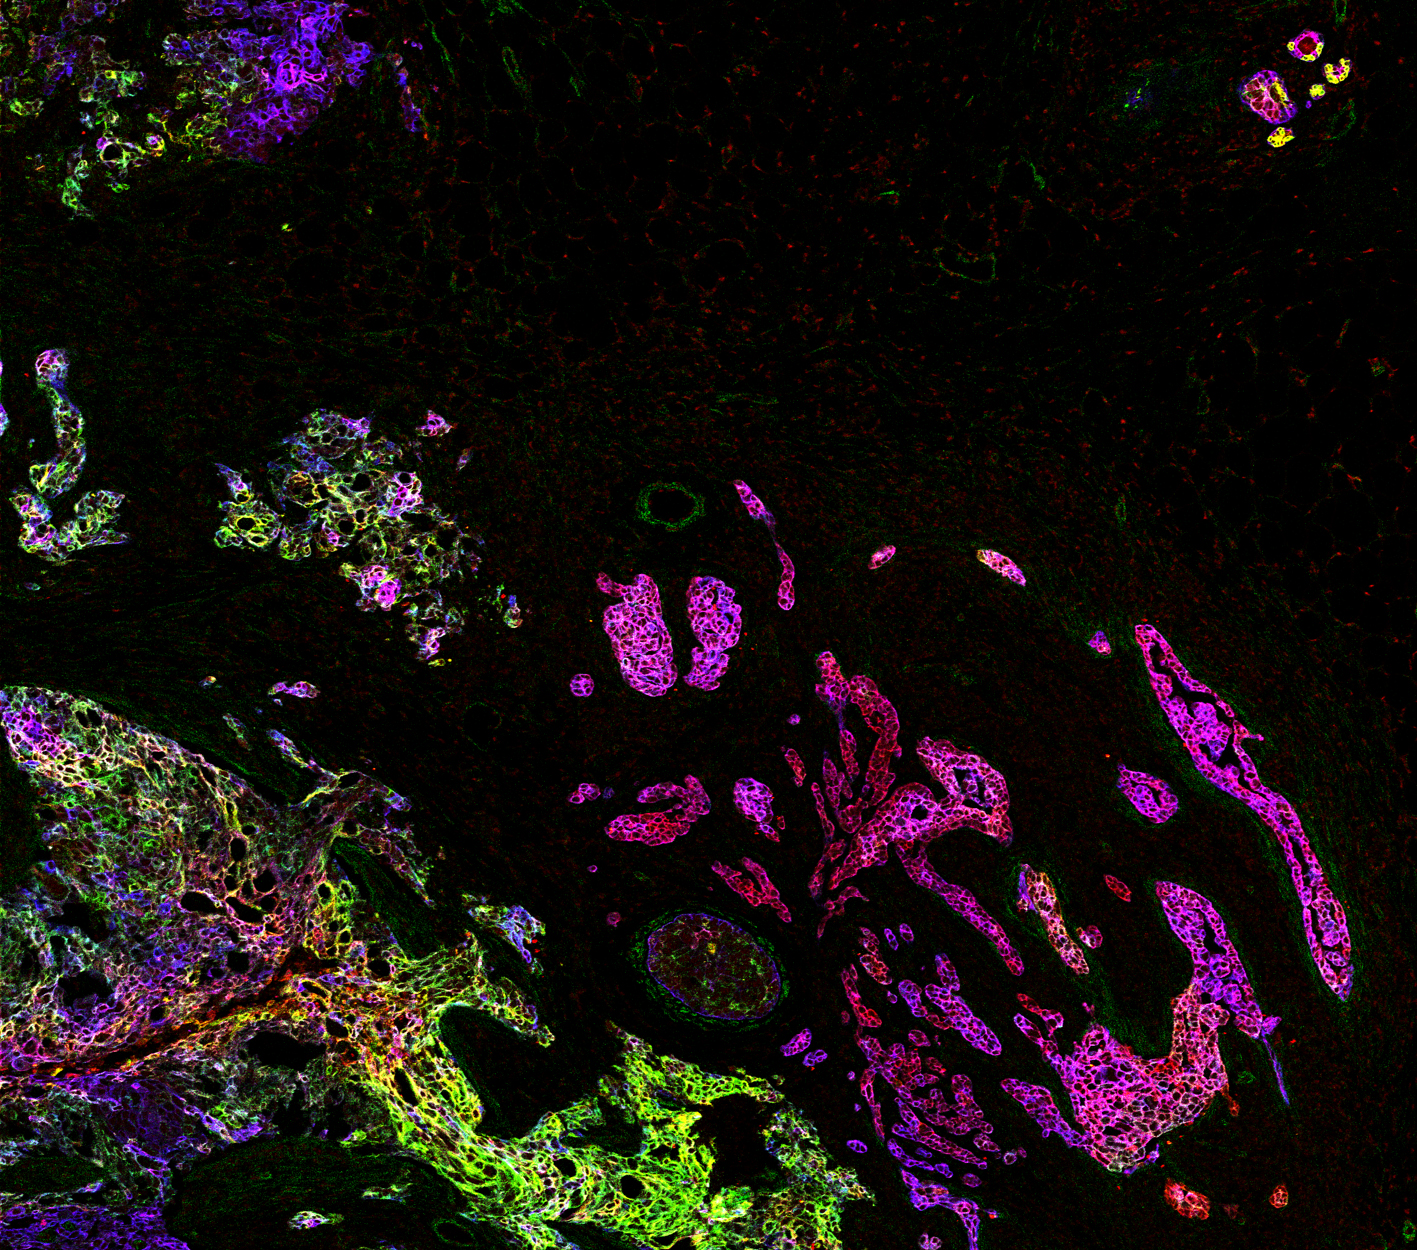

Die Forschungsgruppe um Bernd Bodenmiller, UZH-Professor für Quantitative Biologie, konnte nun mit bildgebender Massenzytometrie die gegenwärtige pathologische Klassifikation verfeinern. Das massgeblich an der Universität Zürich entwickelte Verfahren erzeugt hochaufgelöste digitale Bilder von Gewebeschnitten und ermöglicht es, die überlagerten Informationen von zahlreichen Biomarkern gleichzeitig zu visualisieren und zu analysieren. In der Studie wurden bei rund 350 Brustkrebspatientinnen jeweils 35 Proteine als Biomarker markiert. «So erhielten wir eine hochdimensionale Darstellung der zellulären Landschaft des Tumors und des umliegenden Gewebes», erläutert Jana Fischer, Ko-Erstautorin der Studie.

Das Forschungsteam analysierte auf diese Weise hunderte Gewebeschnitte von Brustkrebspatientinnen und charakterisierte sowohl die Zusammensetzung der vielfältigen Zelltypen als auch deren räumliche Anordnung in multi-zelluläre Gemeinschaften rund um den Tumor. «Aufgrund dieser Daten konnten wir zeigen, dass sich die bestehende Klassifizierung von Brustkrebspatientinnen stark verfeinern lässt. In der Klinik gibt es bislang vier Brustkrebskategorien; wir konnten diese in zahlreiche detailliertere Untergruppen mit unterschiedlichen Risiken unterteilen», erläutert Ko-Erstautor Hartland Jackson.